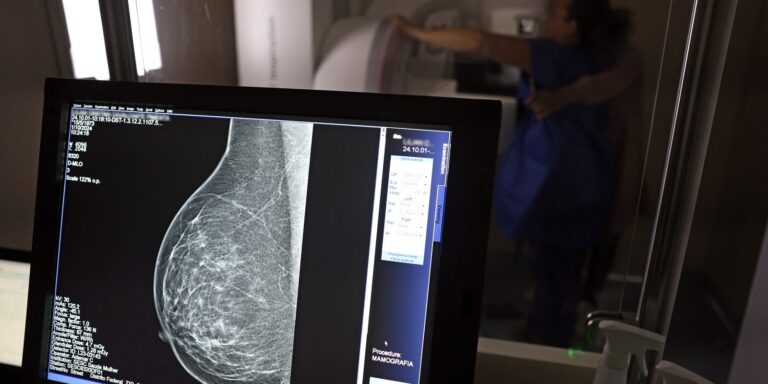

Uma nova lei, publicada nesta segunda-feira (6), reforça o direito do trabalhador com contrato via Consolidação das Leis do Trabalho (CLT) de se afastar até três dias por ano para realizar exames preventivos de câncer, em desconto salarial.

O direito já estava incluído na CLT desde 2018. A partir de agora, as empresas passam a ser obrigadas a divulgar essa informação, além de outras relacionadas a campanhas oficiais de vacinação contra o HPV e sobre o acesso a serviços de diagnósticos de cânceres de mama, próstata e de colo do útero.